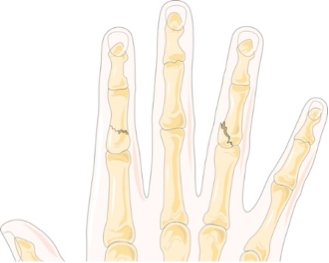

This last graphic illustrating fractures affecting hand strength shows you a fracture of one of the bones of the fourth finger. In this case, the break has occurred in the middle phalanx of that finger. Because so many muscles attach to the phalanges (bones of the fingers), these types of fractures can be quite serious—again requiring splinting or possibly surgery if the bone is displaced. The strength of the entire hand and wrist will suffer because of a break in one of these small bones.

Phalanges Fracture